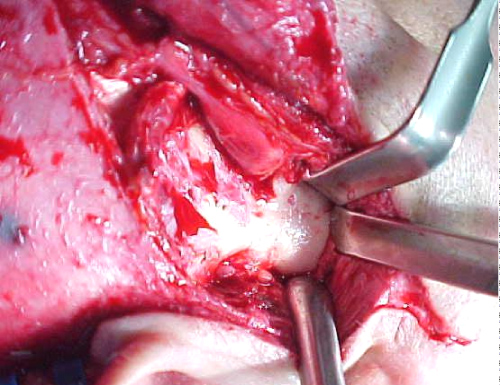

Surgical management of the TMJ ankylosis was decided in order to achieve rehabilitation of the mandible and mastication. A preauricular incision with temporal expansion performed and revealed the articular fossa and the TMJ (Figure 3). Resection of the newly formed bone mass and resection of the coronoid process was performed and the ankylosis of the TMJ was dissolved. The reconstruction of the condyle was achieved with a costo-chondral graft from the 6th rib of the patient (Figure 4), which was fixated in the ramus (Figure 5). The adjustment of the articular fossa performed next, followed by the mobilization of the temporal fascia. The temporal fascia sutured in the region replacing the articular disc and preventing new ankylosis. The function of the joint was tested and the maximum mouth opening showed nearly 40 mm (Figure 6).

Figure 3: Incision showing the TMJ and the newly formatted bone causing the ankylosis. View Figure 3